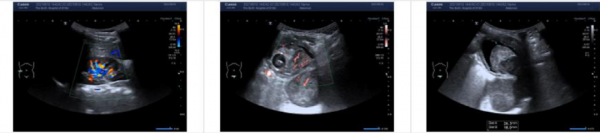

入院後,小兒外科團隊對西西進行全面的系統檢查。泌尿外科副主任、小兒外科主任王德娟團隊邀請中山大學腫瘤防治中心兒童化療科孫曉非教授,泌尿外科、疼痛科、兒科、放射科、超聲科以及藥學部等進行疑難病例討論:鑑於患兒膀胱腫物較大,侵犯部位較多,不宜直接手術治療,先使用化療;並行PET/CT檢查明確有無遠處轉移。

整整兩個多月,四個化療療程,西西掉光了頭髮、眉毛和睫毛。綜合各項檢查結果,化療效果非常顯著,腫物已經有了明顯的縮小。